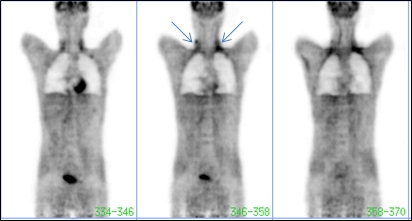

Paciente de 23 años, sexo masculino, con diagnóstico de linfoma de Hodgkin, tratado con 3 ciclos de quimioterapia (ABVD). Se solicita estudio PET con 18F-FDG para evaluar la respuesta al tratamiento.

El estudio mostró acumulación del trazador en región cervical y supraclavicular bilateralmente y de manera relativamente simétrica (fig. 1), con la distribución característica del tejido adiposo pardo. A pesar de las instrucciones recibidas respecto a la preparación para el estudio, el paciente refirió haber estado expuesto a baja temperatura ambiente exterior (unos 7 grados Celsius) sin abrigo adecuado, horas antes del estudio.